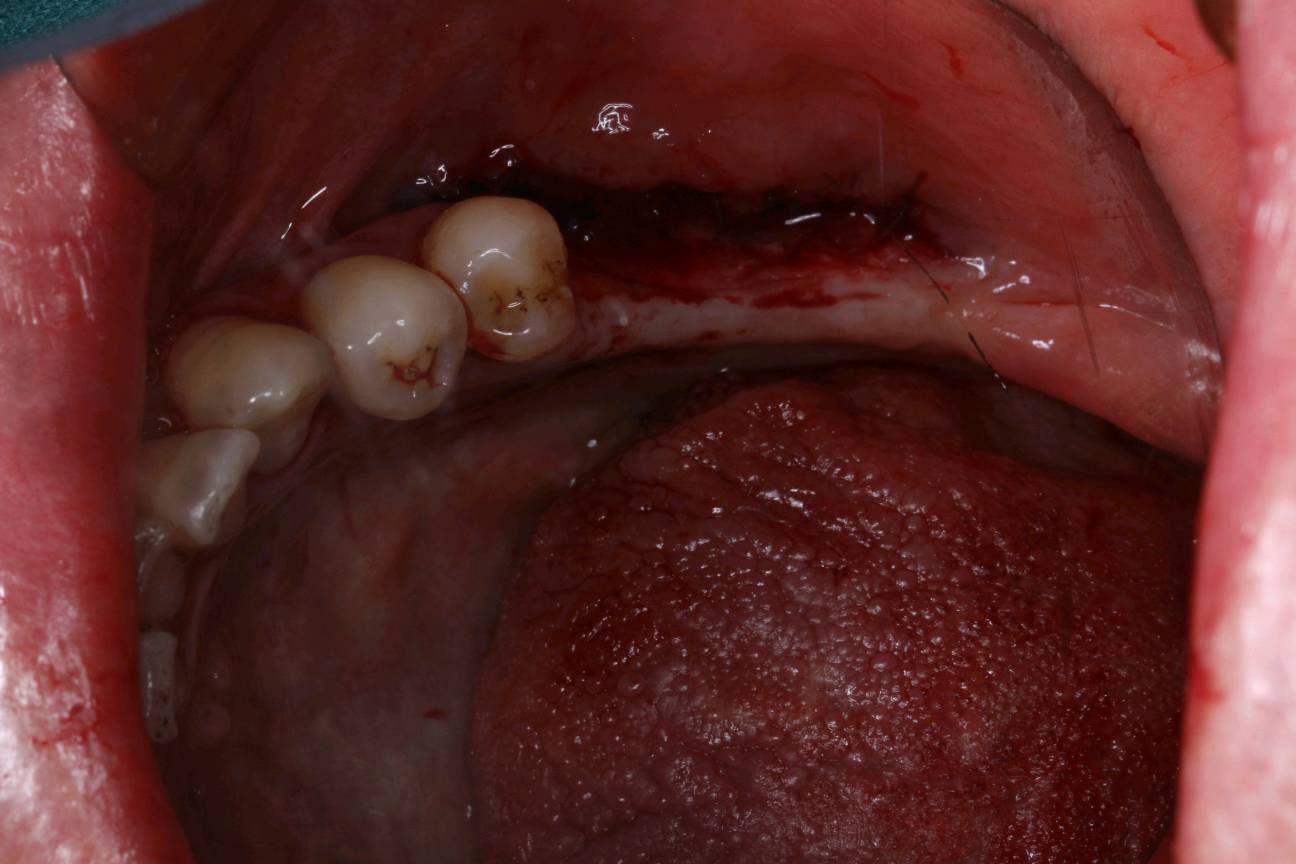

患者女30岁,左下后牙缺失已植入种植体,牙槽嵴呈刀刃壮,附着龈明显不足。角化牙龈缺乏易造成种植体抗炎屏障变弱,容易导致软组织炎症和边缘骨水平吸收。建议患者做游离牙龈移植术。通过获取自体健康游离龈瓣,移植到角化不足的患区,使种植体周围角化组织宽度增加,前庭沟加深。成功的话,会有良好的预后效果。